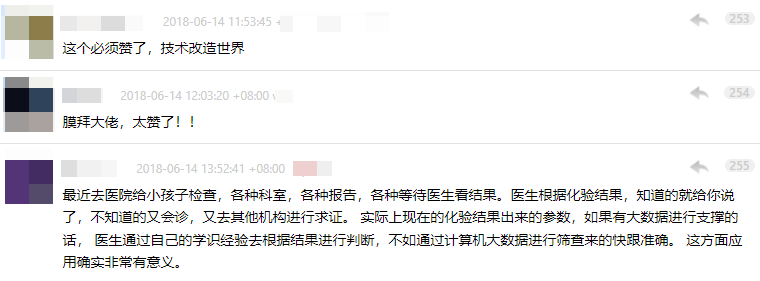

很快,coolwulf 这篇帖子,就获得了罕见的数百条回复。

评论区里,有人正在等待医生的检测结果,焦急难耐;

也有网友家人罹患乳腺癌,对此充满了未知和恐惧。

而 coolwulf 的项目,让他们看到了希望。